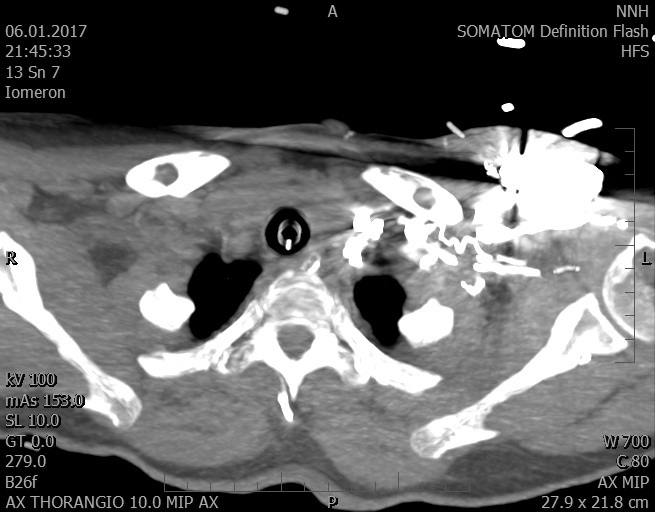

Video 2 - Echokardiograficky byla zjištěna těžká dysfunkce dilatační levé komory s nezvětšenou pravou komorou.Pro nejasnou příčinu zástavy jsme provedli i vyšetření výpočetní tomografií (CT), které vyloučilo plicní embolizaci (série 1 - soubory na konci článku). V den přijetí při přetrvávající oběhové nestabilitě byla nemocná opakovaně defibrilována pro fibrilaci komor se stabilizací rytmu po podání amiodaronu a mesocainu. Dle hemodynamických měření se jednalo o těžký kombinovaný šok. Vstupní laboratorní vyšetření bylo bez větších pozoruhodností. Posléze jsme doplnili anamnézu od příbuzných a zjistili, že pacientka užila do dvou hodin před srdeční zástavou první tabletu amoxicilinu na lehký respirační infekt. Při nevýtěžnosti vstupních vyšetření a nových anamnestických informacích jsme doplnili 14 hodin po kolapsu vyšetření koncentrace tryptázy v séru, která byla extrémně zvýšena (tabulka 2), což nás vedlo k podezření na anafylaxi.